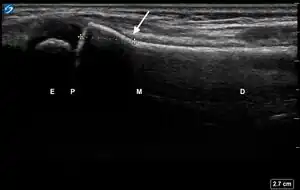

| Secondary Signs of Pediatric Distal Forearm Cortical Break Fractures | # | Sonographic Signs | Ultrasound Image |

| 1 | Angulation of the distal bone segment[14] | ![]() | |

| 2 | Fracture < 1 cm from physis | ![]() | |

| 3 | Periosteal hematoma[14][15] | ![]() | |